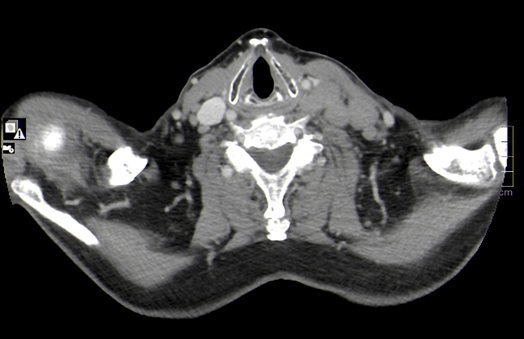

Se observan ganglios aumentados de tamaño con afectación cervical, torácica, abdominal, pélvica e inguinal.

DIAGNÓSTICO FINAL: linfoma no hodking tipo B.